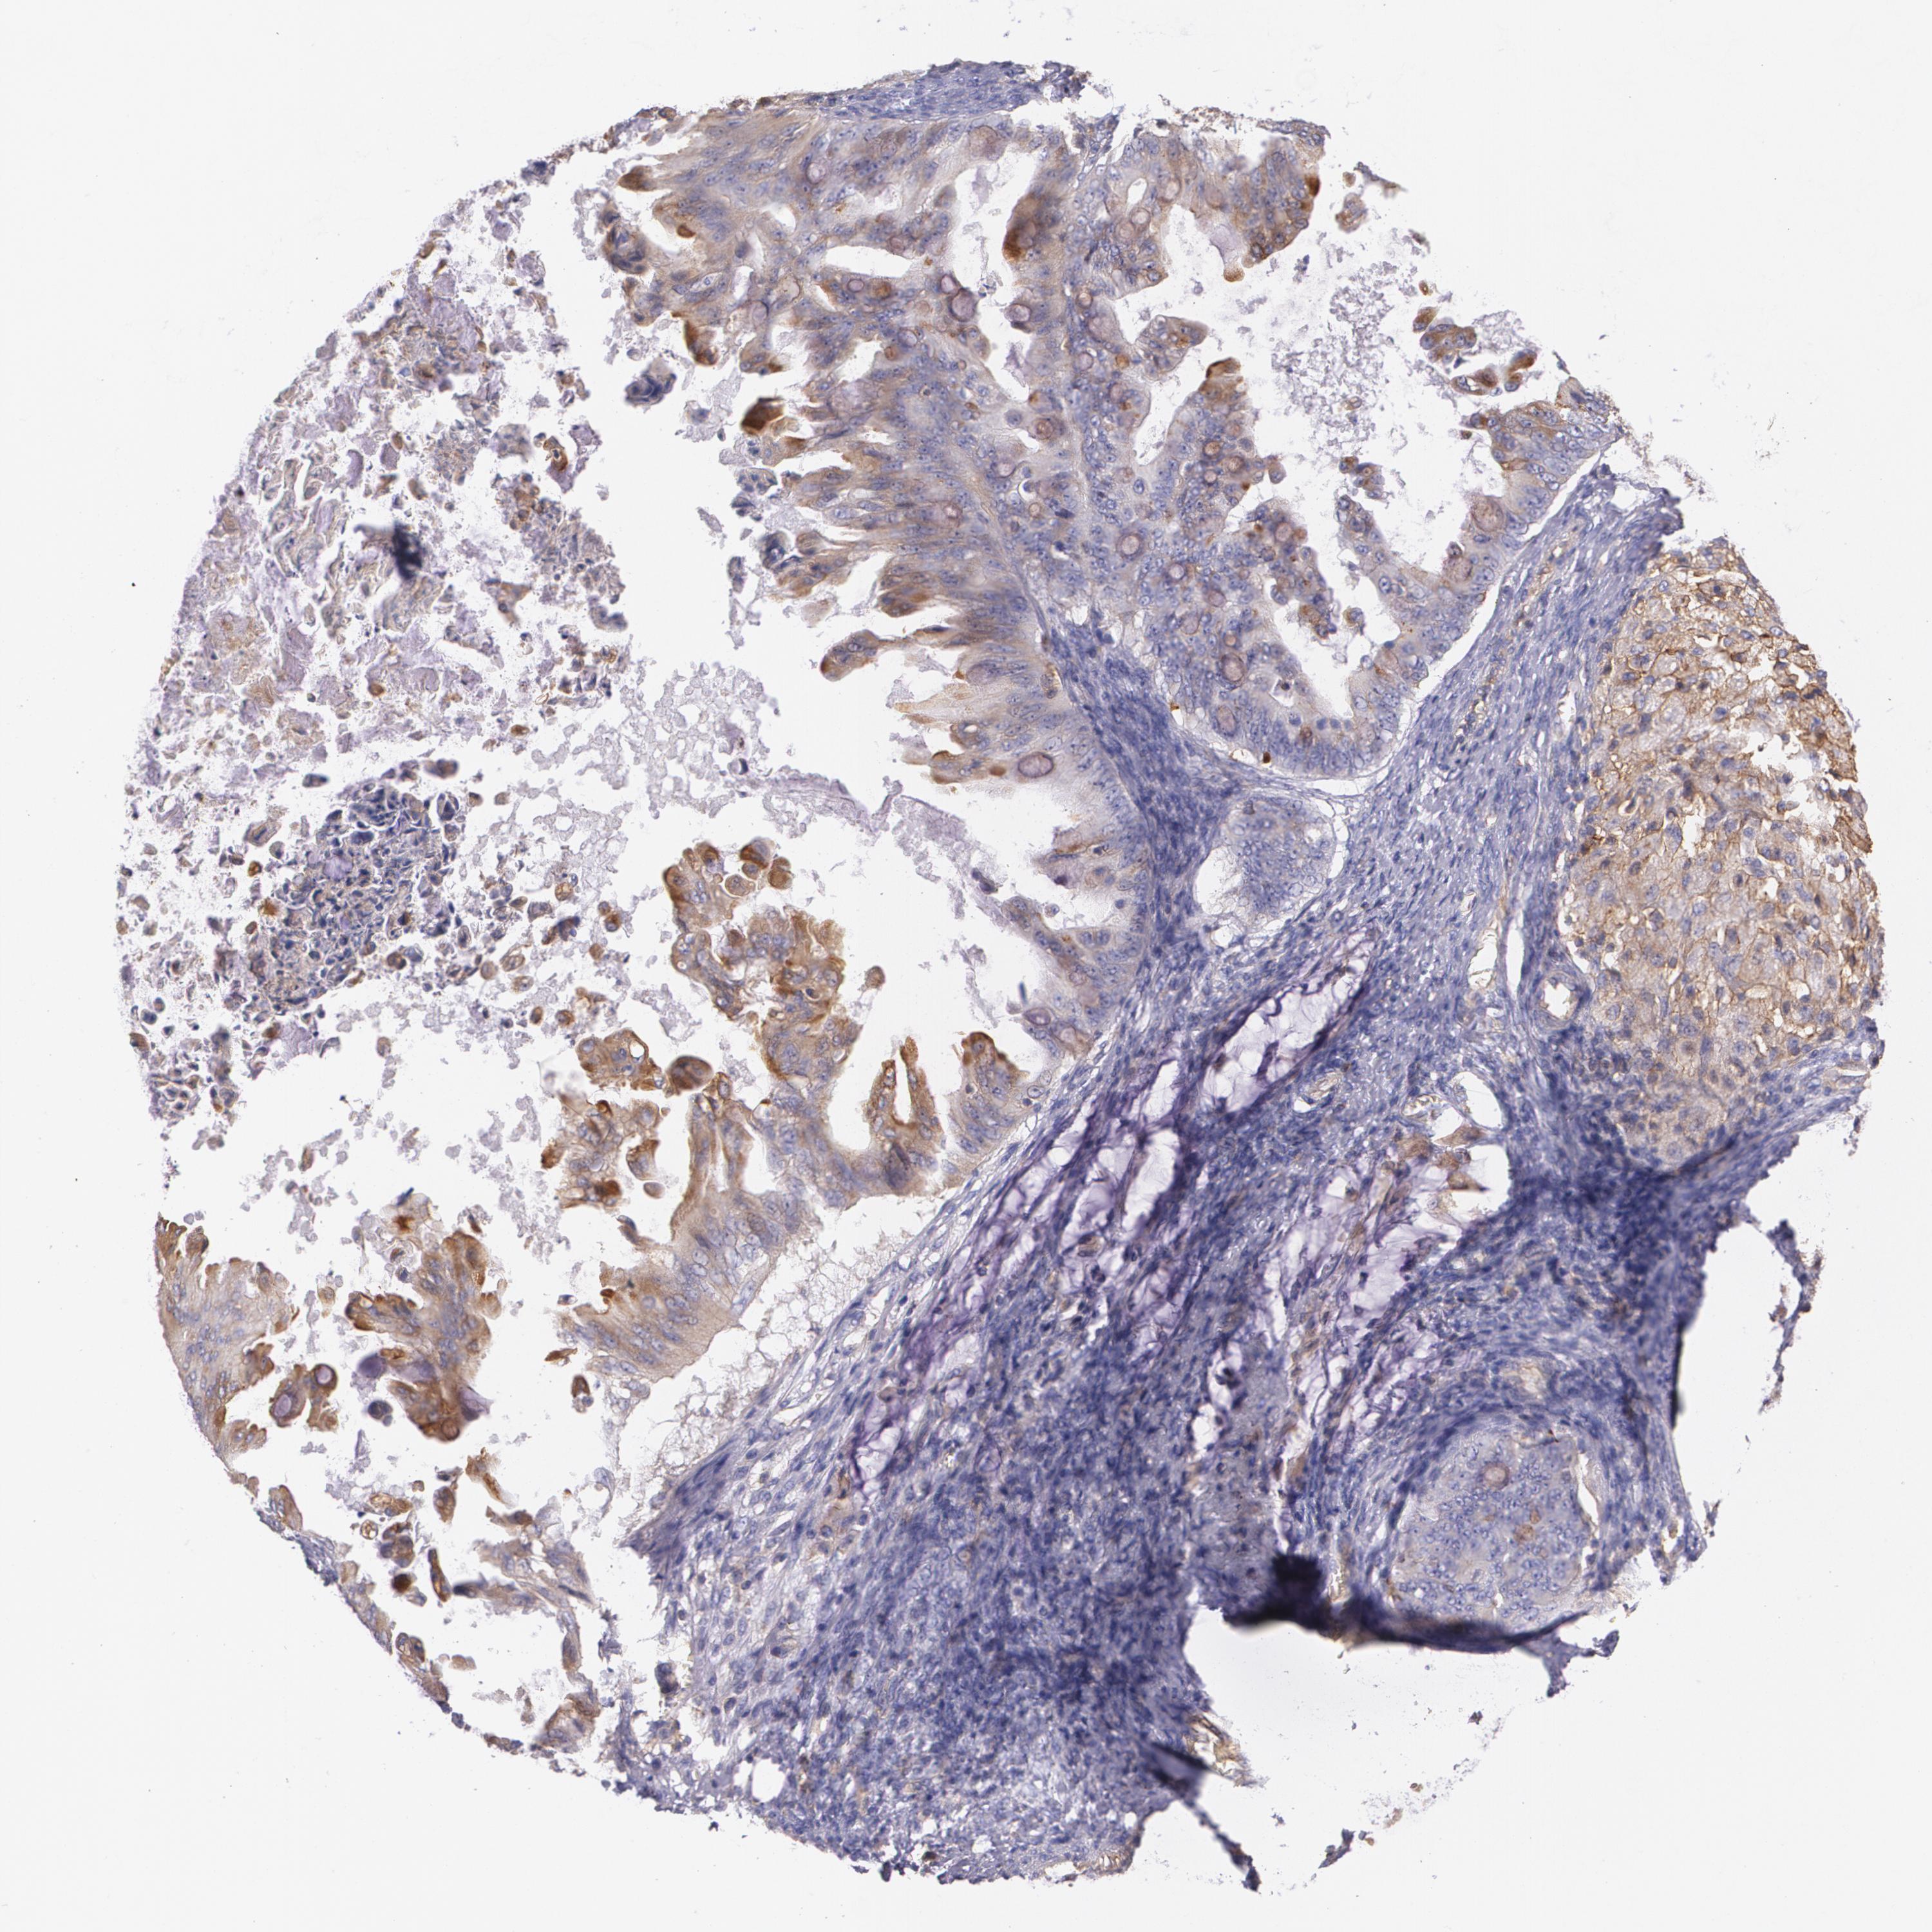

OVARIAN CANCER - Protein expressioni

A mouse-over function shows sample information and annotation data. Click on an image to view it in a full screen mode. Samples can be filtered based on level of antibody staining by selecting one or several of the following categories: high, medium, low and not detected. The assay and annotation is described here.

Note that samples used for immunohistochemistry by the Human Protein Atlas do not correspond to samples in the TCGA dataset.

Antibody stainingi

Antibody staining in the annotated cell types in the current human tissue is reported as not detected, low, medium, or high, based on conventional immunohistochemistry profiling in selected tissues. This score is based on the combination of the staining intensity and fraction of stained cells.

Each image is clickable and will lead to virtual microscopy that enables deeper exploration of all samples and also displays staining intensity scores, fraction scores and subcellular localization as well as patient and tissue information for each sample.

Antibody HPA006361

Cystadenocarcinoma, serous, NOS

Carcinoma, endometroid

Carcinoma, NOS